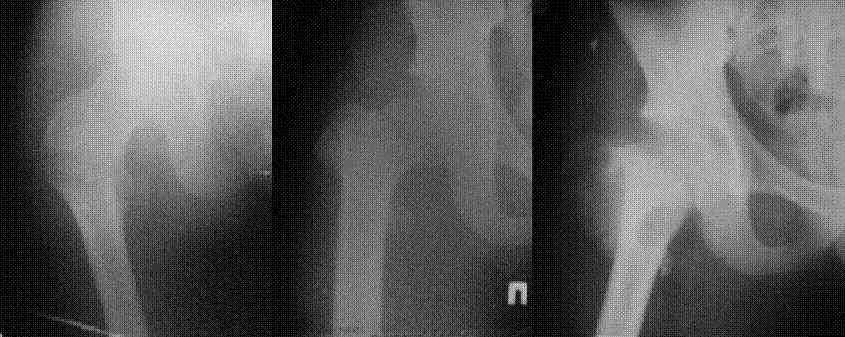

В приложении пример пациента, близкого по картине к тому, что представил Виктор (варус и смещение периферического отломка на поперечник кзади). Сделали как раз то, что Виктор исходно намеревался - аппаратная коррекция и затем гамма.